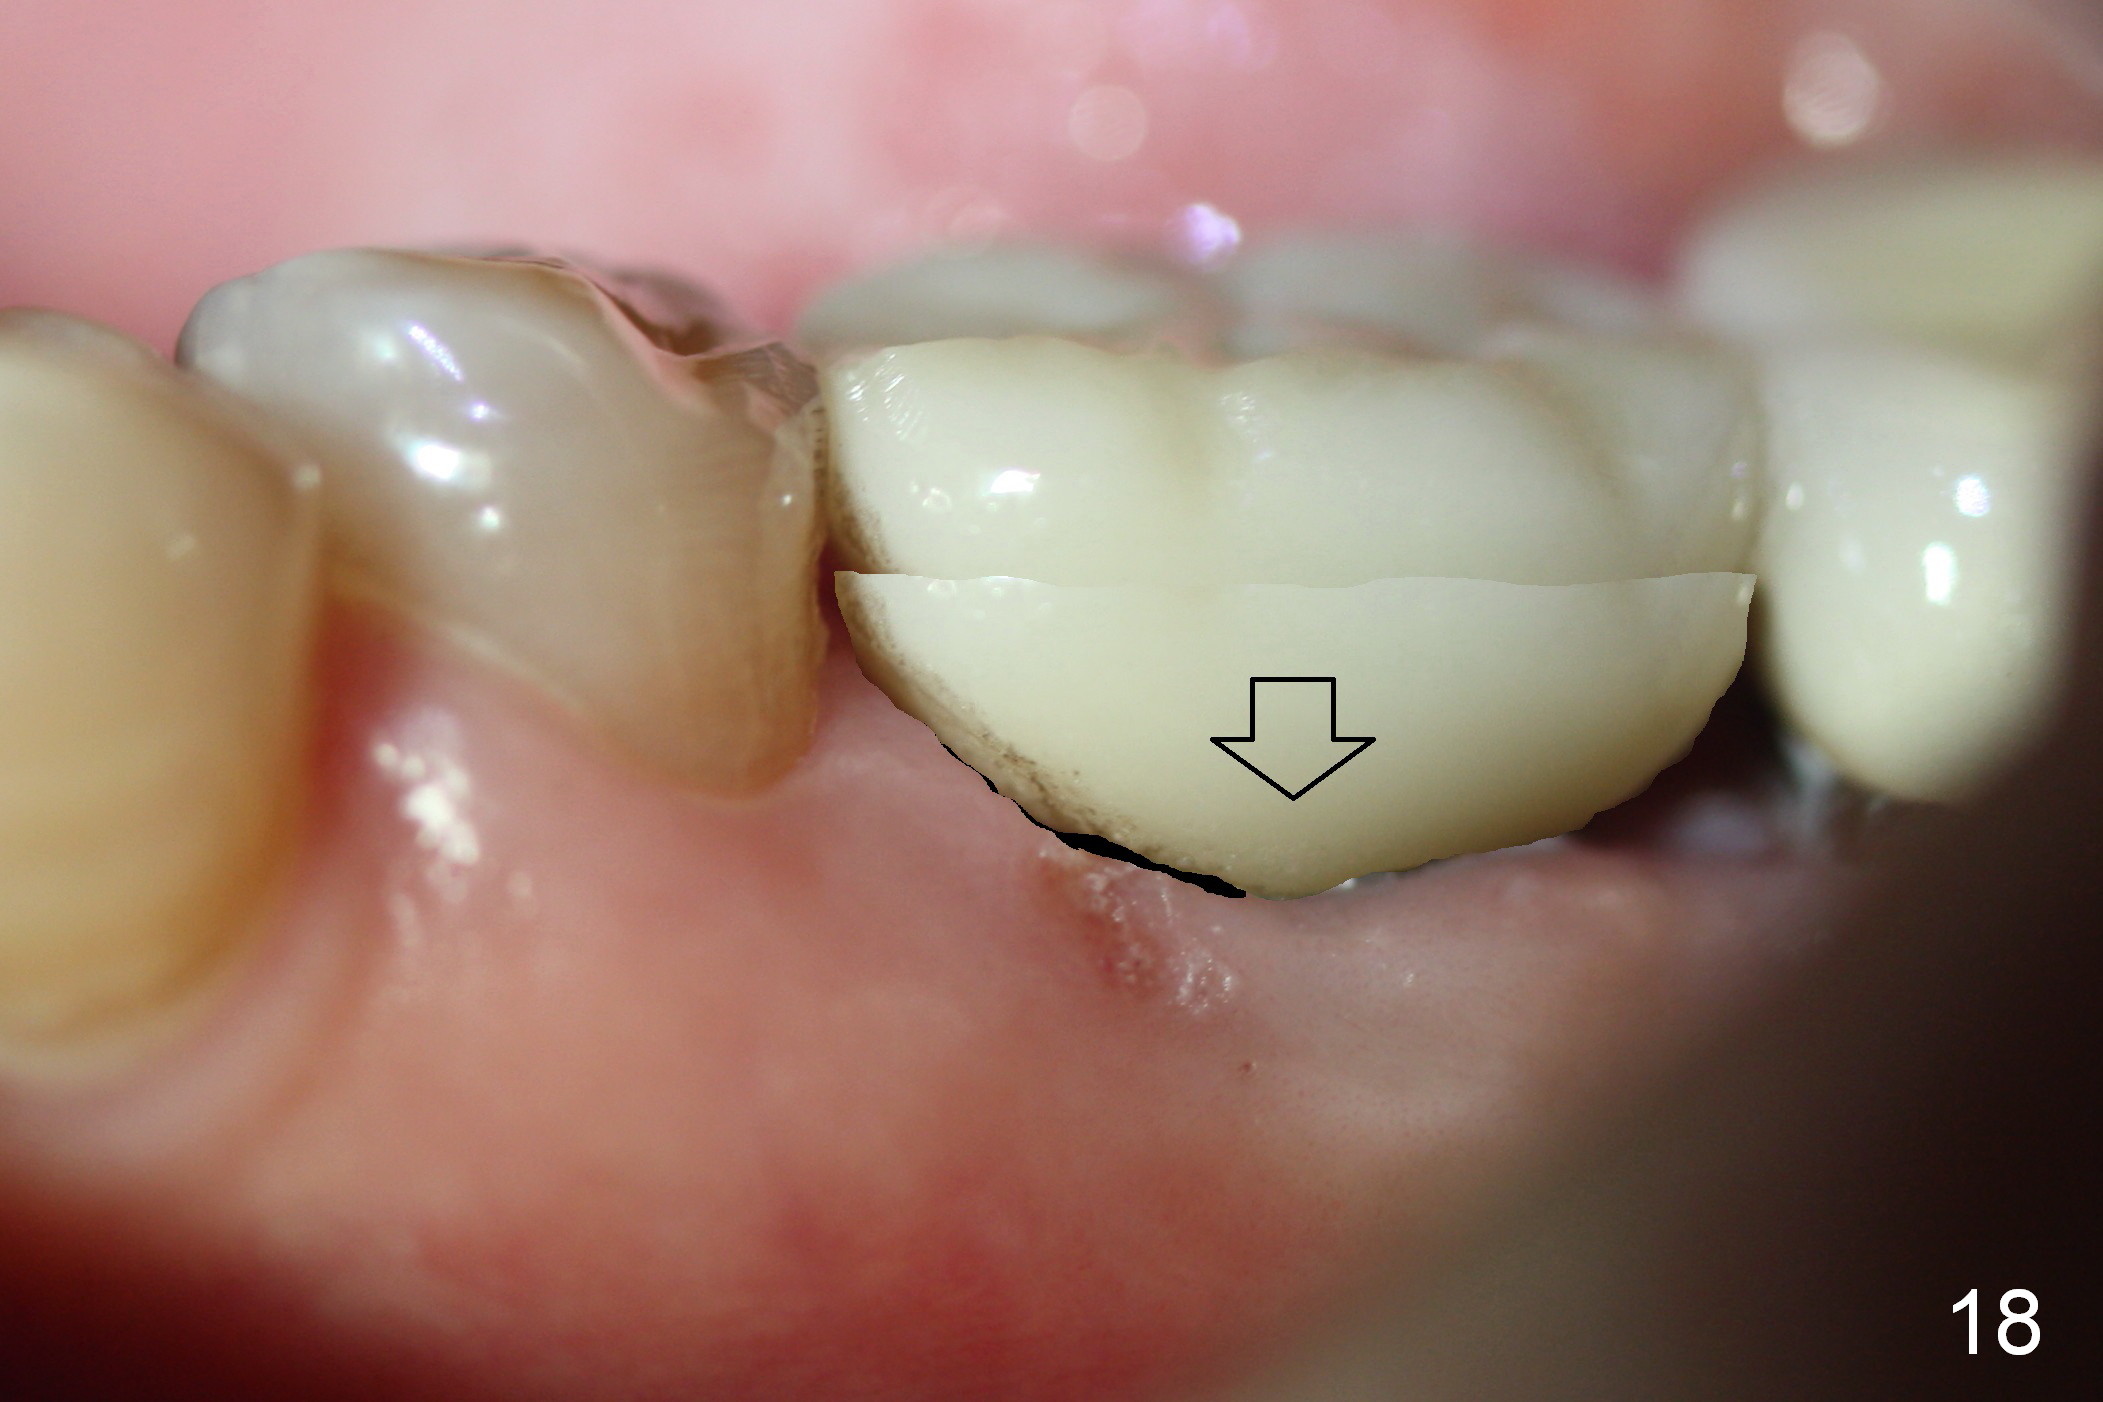

After removing the crown, the margin is lowered clinically. In the lab, the mesial gingiva in the model is to be trimmed ~1 mm (Fig.17 arrow (black area)) so that the mesial embrasure is closed as much as possible (Fig.18). The contact area is larger both buccolingually and apicocoronally. Clinically, the mesial margin of the temporary crown should be a little bit bulging to push the mesial papilla mesially so that there is enough space to clean cement for the permanent crown.